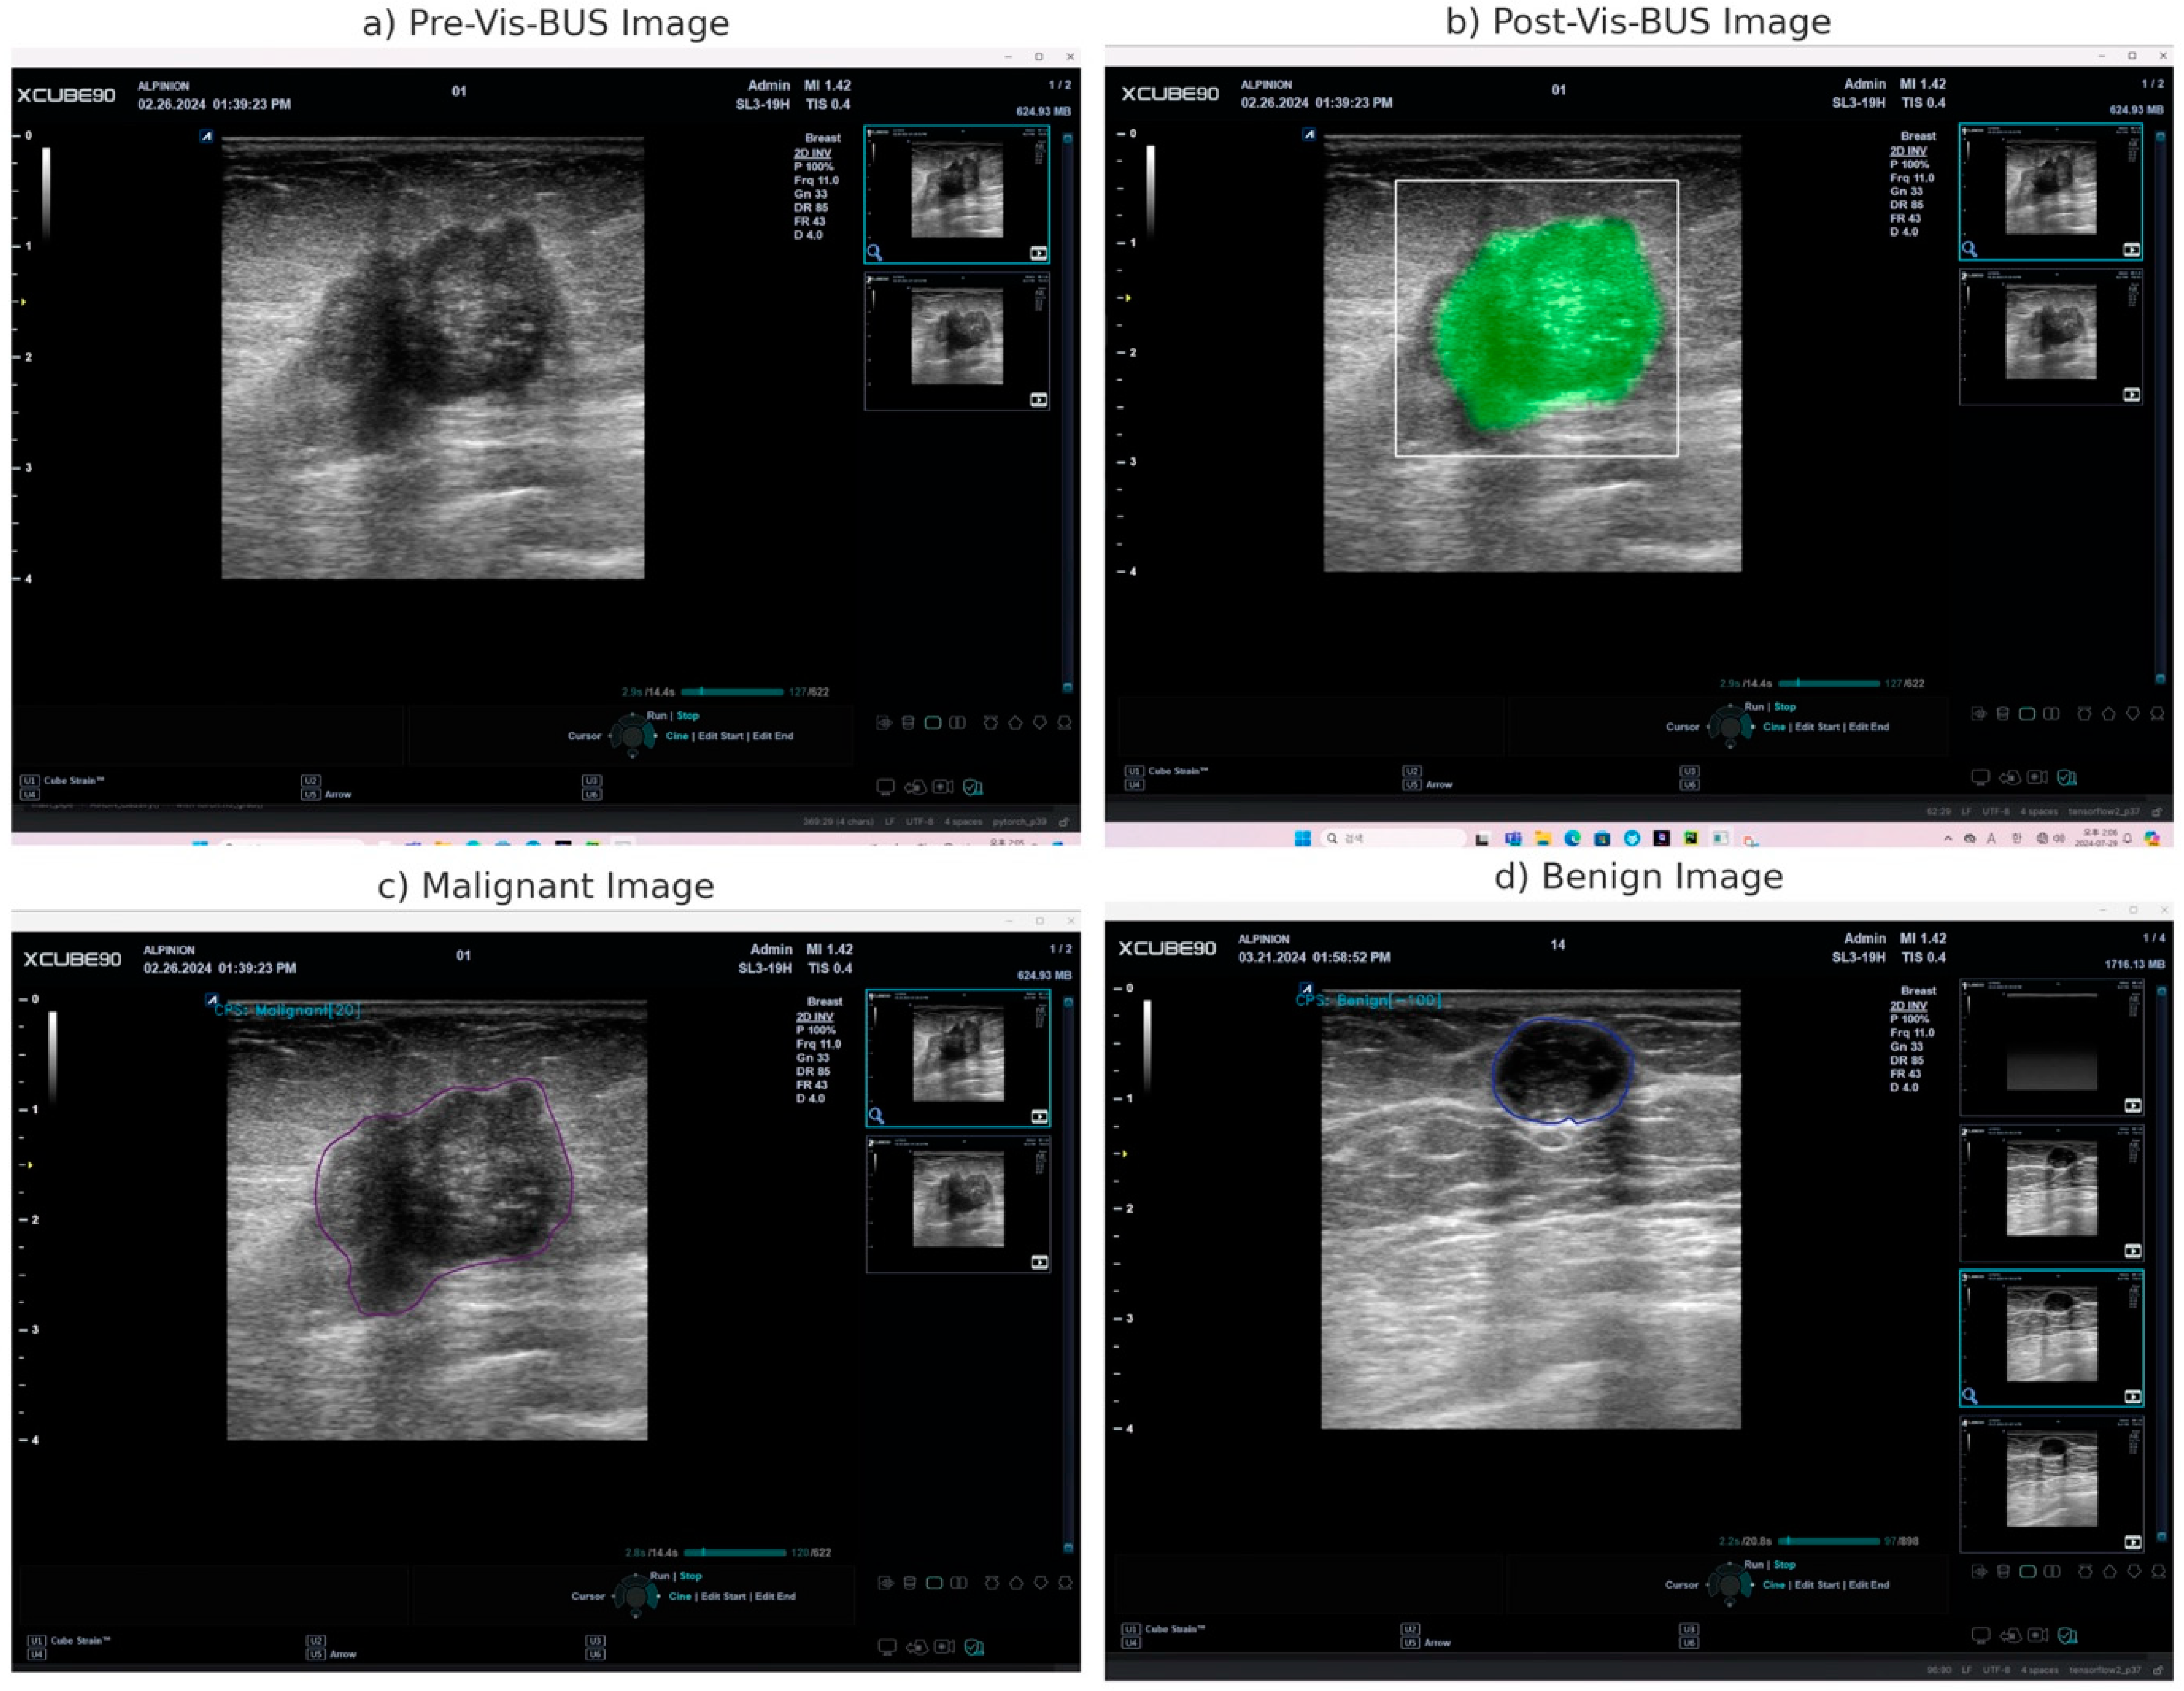

2.4. Explanation of Vis-BUS Operation

| Real-time Diagnostic Insights | Vis-BUS processes live ultrasound images and provides immediate diagnostic feedback. | High-resolution quantitative analysis with real-time feedback, effectively highlighting pathological features. |

| Post-Analysis on Freeze Frames | Detailed examination of static ultrasound images using the AI tool. | Maintains diagnostic precision even when analyzing static images, ensuring thorough evaluation of specific frames. |

| Cancer Probability Score (CPS) | Quantitative assessment of the likelihood of a lesion being malignant or benign, displayed on a scale from −100 to 100. | Accurate differentiation between benign and malignant lesions, aiding in informed clinical decision-making. |

| Lesion Characterization | Analysis of key pathological features such as tissue texture, echo patterns, and microcalcifications. | Precise identification of lesion characteristics, contributing to the accurate classification of breast lesions. |